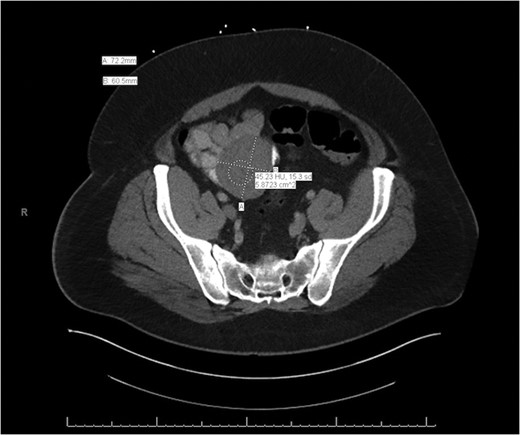

A CT of the abdomen and pelvis without contrast was obtained on admission and revealed a 7 × 7.6 cm2 mass with CT attenuation of 37.34 Hounsfield units within the anterior left midpelvis. It appeared to be inseparable along its superior aspect from a loop of bowel, and it was felt to possibly be an unusual diverticulum. The patient was given intravenous fluids and one unit of packed red blood cells for his symptomatic anemia with continued rectal bleeding. He was also empirically started on Cipro and Flagyl for possible infection coverage. GI was consulted and the patient was taken for an EGD and colonoscopy; however, both were negative for any acute pathology.

General surgery was then consulted for further recommendations. A CT of the abdomen and pelvis with contrast was performed and demonstrated a 7.2 × 6.8 × 6.1 cm3 lesion arising from the mid-to-distal small bowel loop with no evidence of significant enhancement. It appeared mobile within the mesentery of the small bowel when compared to previous imaging (Figs. 1 and 2). The patient had continued to bleed and required transfusion with five units of packed red blood cells; therefore, it was decided to take the patient to the operating room for a diagnostic laparoscopy.

Axial slice of the CT of the abdomen/pelvis demonstrating a lesion arising from the mid-to-distal small bowel.